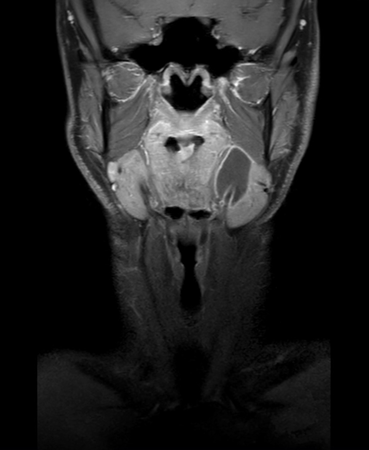

Coronal mDIXON XD - T2w TSE (Water only)

Coronal mDIXON XD - T1w TSE (Water only)